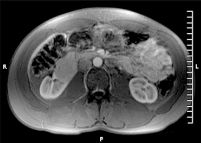

Mass in the anterior portion of the right kidney